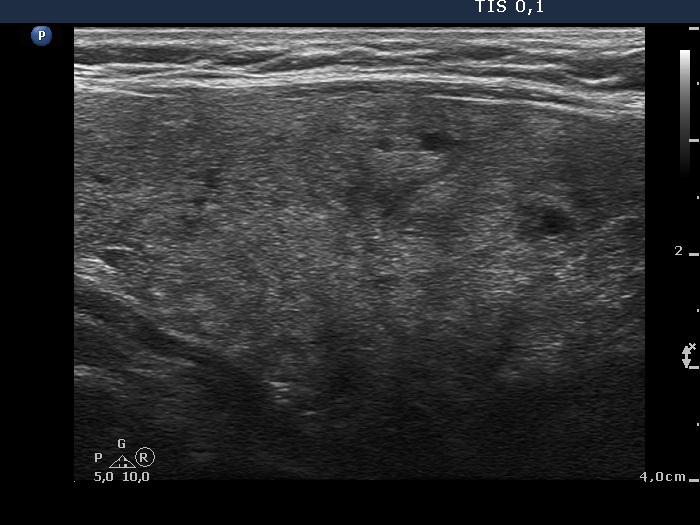

Consecutively operated patients with autoimmune thyroid disease - case 54 (1354) (ultrasonographic picture 6)

Left lobe, another longitudinal view.